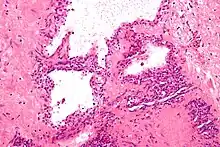

| Micrograph showing a pancreatic serous cystadenoma, a type of cystadenoma. H&E stain. | |